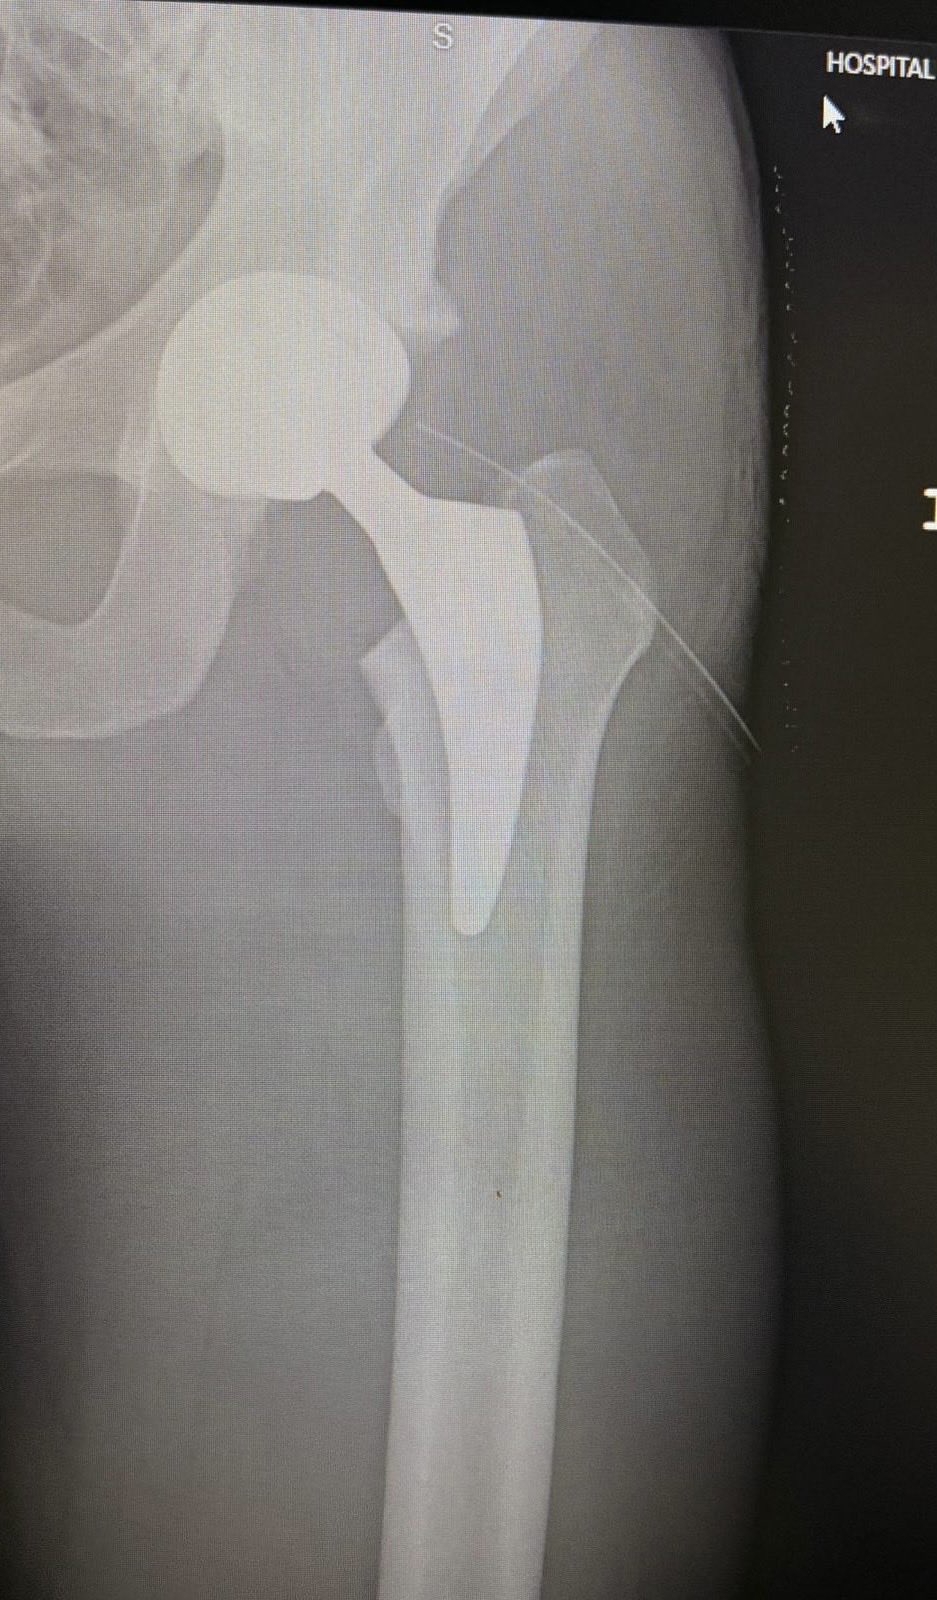

ستاره آرژانتینی با انتشار تصویری از نتیجه عمل جراحی خود که در آن بخش آسیبدیده مفصل با یک قطعه مصنوعی جایگزین شده، نوشت: «کمی درد دارم اما با لگن جدیدم بهتر خواهم شد. امیدوارم این پروتز شروعی برای یک زندگی بدون درد باشد.» لاملا که در زمان بازنشستگیاش فاش کرد در سال ۲۰۱۷ و در حالی که ۲۵ سال داشت و به خاطر مشکل این مفصل زیر تیغ جراحی رفته بود در آن زمان پزشکان به او گفته بودند که تنها ۴ سال دیگر میتواند فوتبال بازی کند. در تمام آن سالها، زندگی و تمرین با درد، روتین تکراری روزهای او بود.